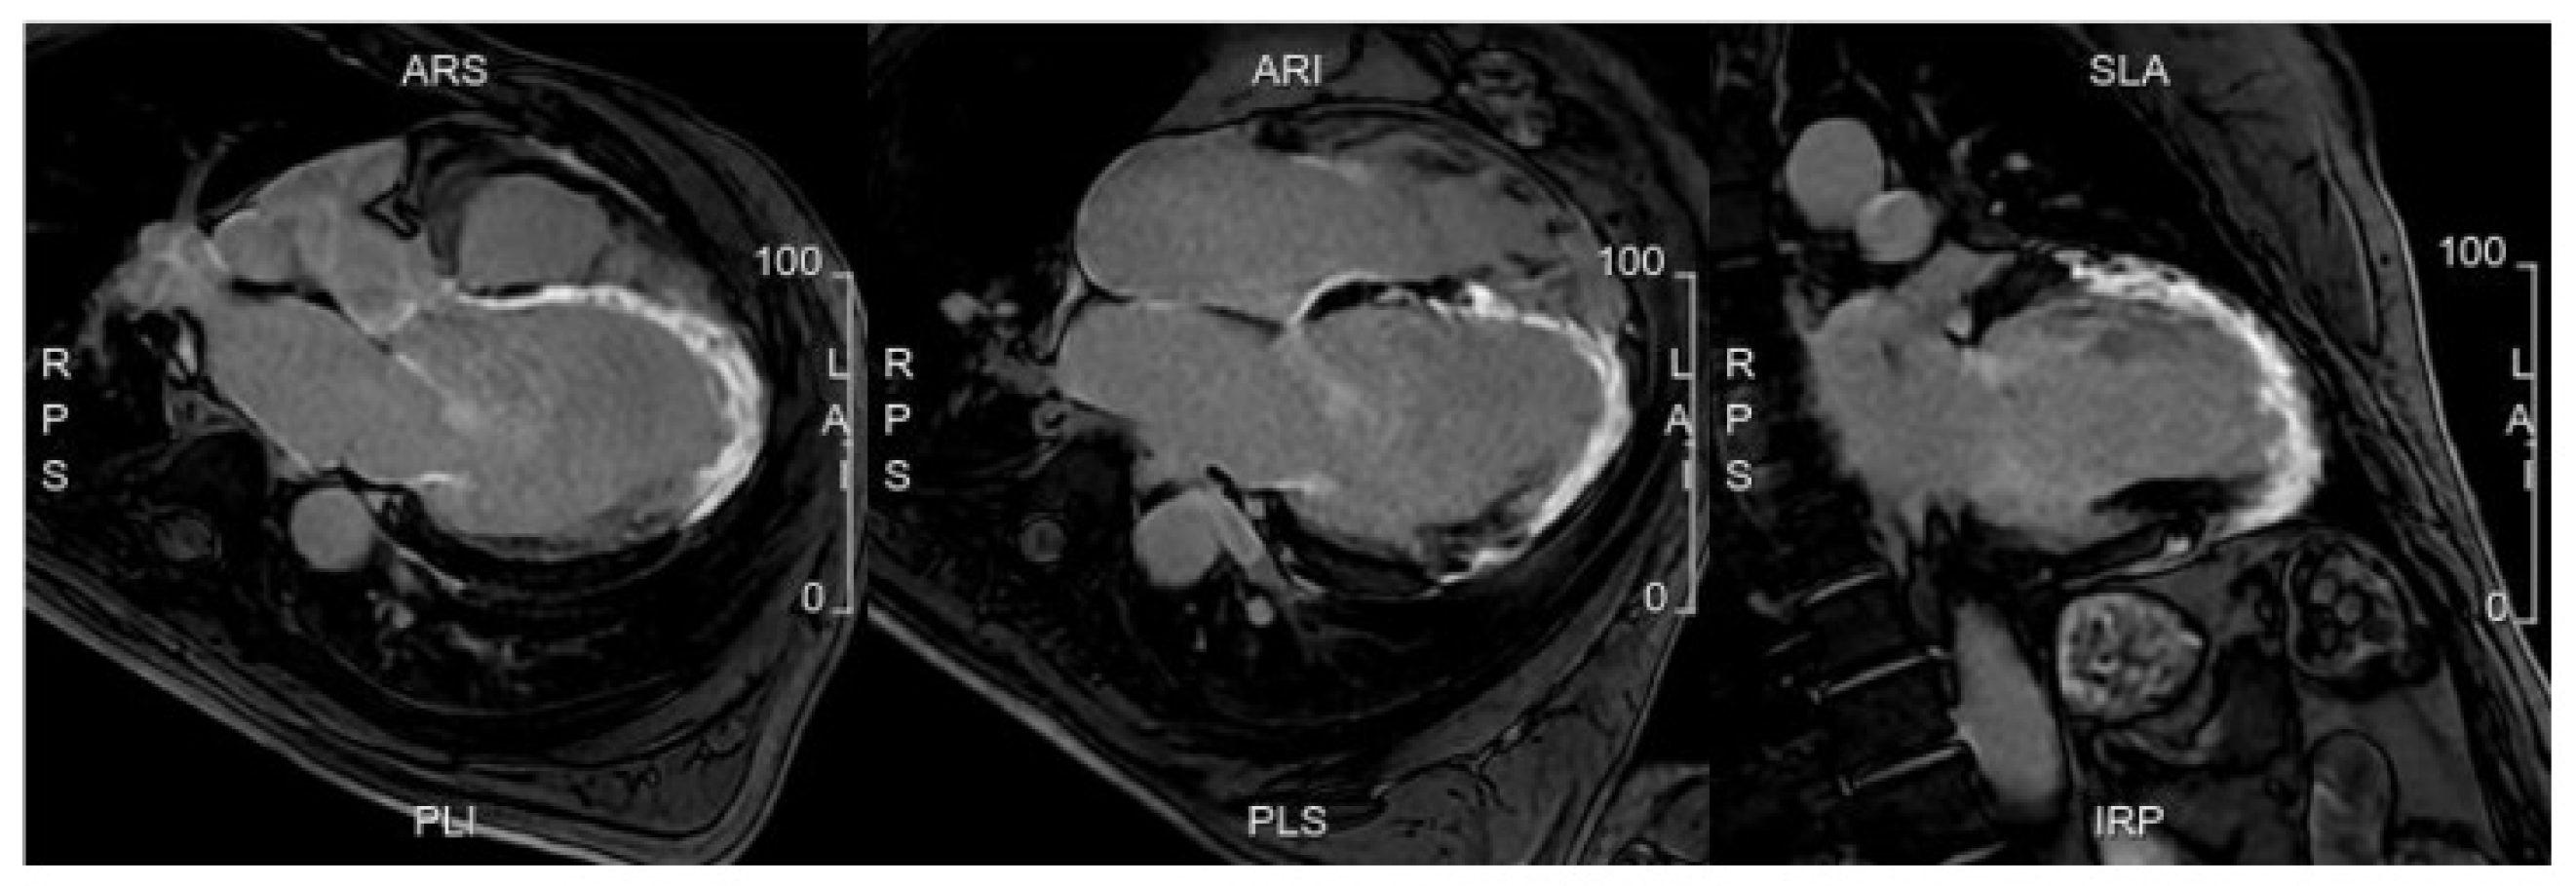

Coronary computed tomography angiography (CCTA) is a non-invasive imaging test widely used in daily practice. Its validity and feasibility in the diagnosis and risk stratification of CAD are well established (Figure 1). CCTA has replaced coronary angiography as a diagnostic tool for confirming CAD. Indeed, CCTA is useful for ruling out CAD with an intermediate or low pre-test probability due to its high negative predictive value (NPV) [14]. Numerous randomized controlled trials (RCTs) have confirmed the effectiveness and potency of CCTA in this field [15,16,17].

Figure 1.

A patient with a strong family history of CAD, with cardiac CT positive for non-obstructive CAD on proximal LAD (panels A,B). A high-risk fibrolipidic plaque (red arrow) with positive remodeling, low attenuation, and small spotty calcification is evident in both the long (panel C) and short (panel D) axis views.